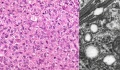

恶性组织细胞病